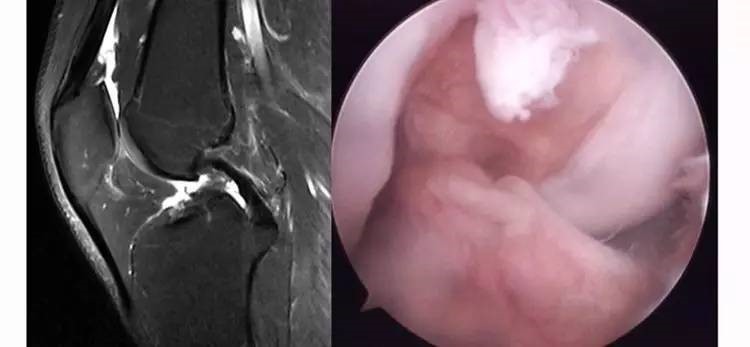

6.扭曲和空虚:髁间窝内似隐隐约约有低信号,边缘明显,中央空虚;或者中央有低信号,但扭曲如麻花状。多为陈旧损伤,仅存ACL的滑膜,里面可有少量的韧带纤维,粘附在后方,随着膝关节的长时间屈伸逐渐呈扭曲状。

13.gif